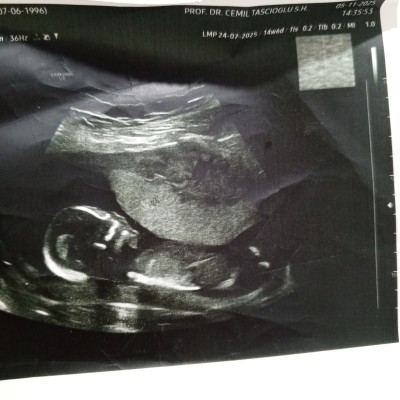

Kızlar devlet hastanesinde ikili test sonucunu almak için perinatolojiye randevu almıştım 14+6 haftalıkken. Dr hızlıca ultrasonla baktı cinsiyet sordum direkt erkek dedi ama çok detaylı incelemedi. Yanılma ihtimali olur mu? Perinatoloji olduğu için cihazları daha iyidir diye düşünüyorum. Sağlıklı olsun iki kızım var, oğlum olsun da isterim

image